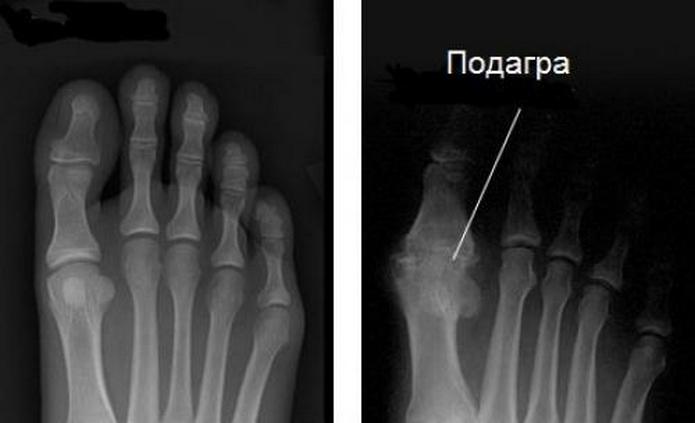

Диагностика

Диагностика предусматривает визуальный осмотр пораженного подагрой сустава, проведение рентгенографии, а также лабораторные анализы крови и мочи. Рентген позволяет определить состояние сочленения, наличие остеофитов. Лабораторные анализы дают возможность отметить повышенный уровень мочевой кислоты в крови. Симптомы и признаки, описанные пациентом с подагрой, помогают назначить адекватное лечение. В зависимости от степени концентрации мочевой кислоты в организме пациента ему могут быть назначены лекарства, способствующие ее выведению.